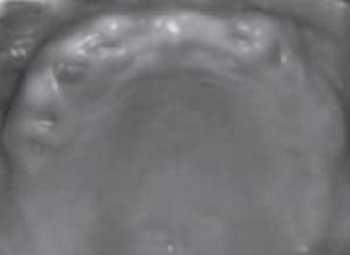

1.2.3治療過程:先行微創(chuàng)拔除14、13、21、22、23、24及25,搔刮拔牙窩去除炎癥組織,常規(guī)制作一副上頜過渡義齒(圖4,5)。2個月拔牙術后復診,利用上頜過渡義齒作為個性化托盤取上頜模型并翻制石膏模型,在石膏模型上根據(jù)過渡義齒標出各個牙位,同時利用壓膜機制作放射性模板(如圖6)。患者佩戴放射性模板拍攝全景片及CBCT(如圖7、8)。

圖4 微創(chuàng)拔除術后口內(nèi)照

圖5 上頜過渡義齒修復口內(nèi)照